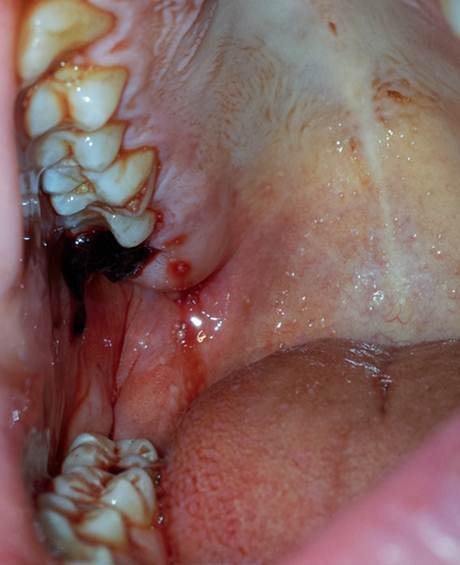

Pour une scène il faut faire un effet que l'acteur a une dent molaire arraché. C'est assez frais, mais pas à l'instant. Disant lendemain. Comme sur l'image

Est-ce qu'il faut prendre le vernis noir à dent et un peu de sang ou peut-être il y a autre chose plus crédible ? (Oui, je sais, on peut directement arracher la dent et l'acteur économisera chez dentiste :twisted: )